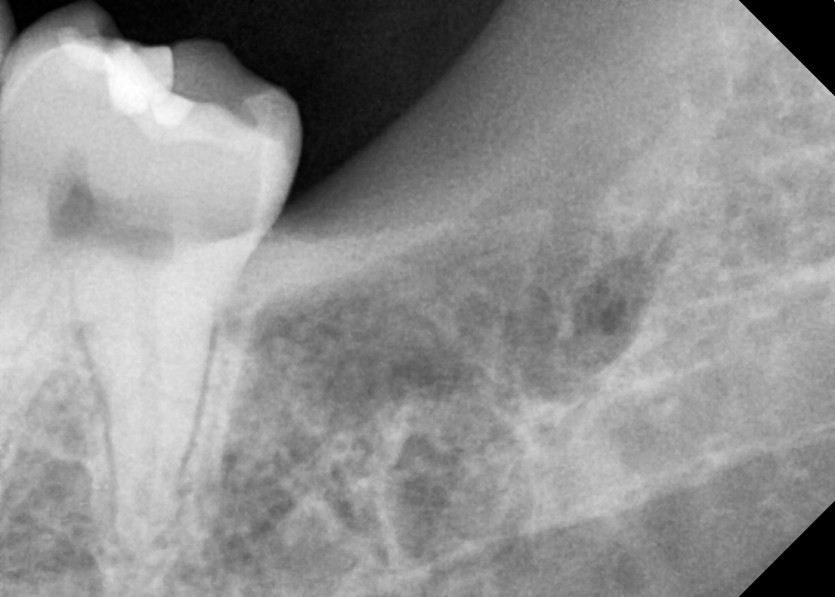

#38 사랑니 발치

구강 외과 전문의가 당일 발치했습니다.